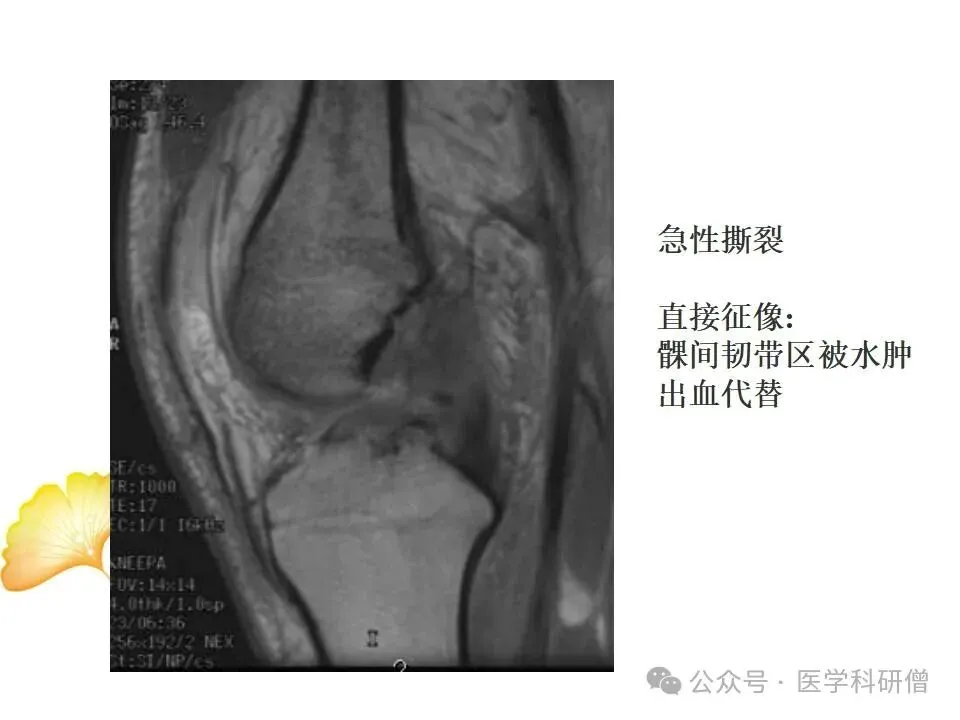

• T2加权像:对于显示水分和炎症特别敏感,能够显示韧带周围的水肿和炎症情况,对于诊断韧带损伤非常有帮助。

通过这些技术,医生能够准确判断韧带的损伤类型、程度和范围,从而制定出合适的治疗方案。